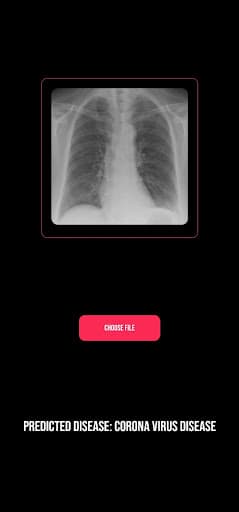

ProjectK is an AI-powered app that can detect pulmonary diseases by analyzing lung X-rays. I made it during a hackathon.

Screenshot 1 of ProjectKScreenshot 2 of ProjectKScreenshot 3 of ProjectKScreenshot 4 of ProjectKScreenshot 5 of ProjectKScreenshot 6 of ProjectK